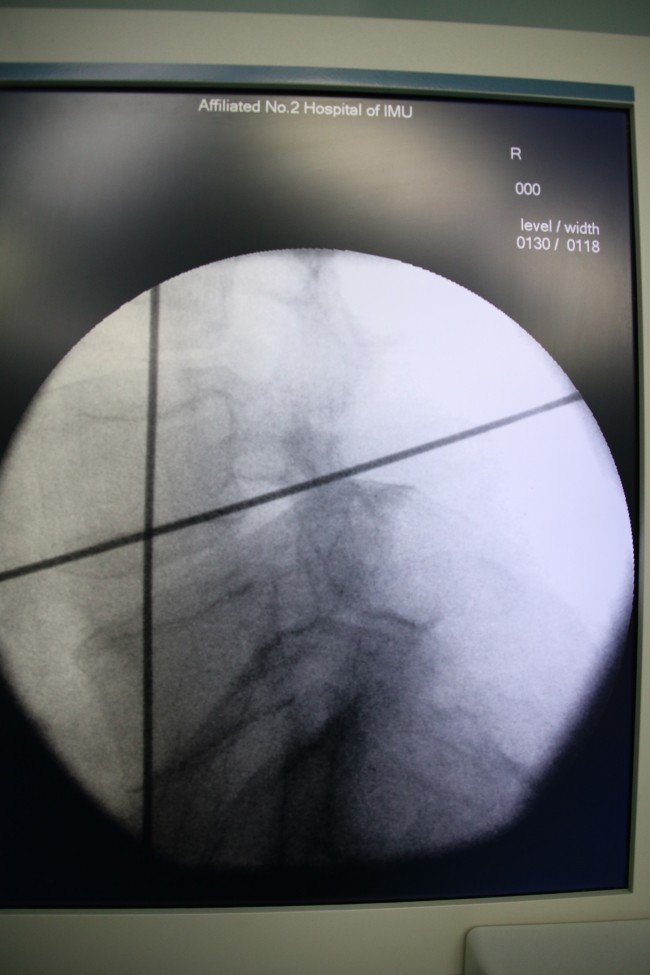

近年来,随着脊柱微创理念的更新以及微创技术不断发展,“靶点”治疗得到广大医学同道及患者的高度认可,常规脊柱手术逐步微创化、可视化、有限化及智能化。而OLIF(即斜外侧入路椎体间融合内固定术)治疗腰椎不稳定正是其中之代表。此项技术仅使用于腰椎不稳定伴或不伴轻度椎管狭窄,以及椎间盘源性痛的患者。此例手术皮肤切口约4cm,经腹膜外、腰大肌前缘入路,术中出血量仅为25mL。因其术中出血少,不干扰椎管内结构,对腰大肌及腰背肌无影响,无需引流,术后72小时即可下地活动,并发症发生率低,术后恢复快,住院时间短,治疗费用低,患者易于接受。